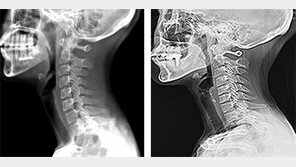

목을 숙여 스마트폰을 보는 습관 등으로 목, 어깨 등에 뻐근한 통증을 호소하는 ‘일자목 증후군’ 환자가 매년 증가하고 있다. 일자목 증후군이란 목을 길게 빼는 자세 때문에 C자 형태의 경추가 일자로 변형되는 질환이다. 국민건강보험공단에 따르면 ‘일자목 증후군’ 환자는 2011년 239…